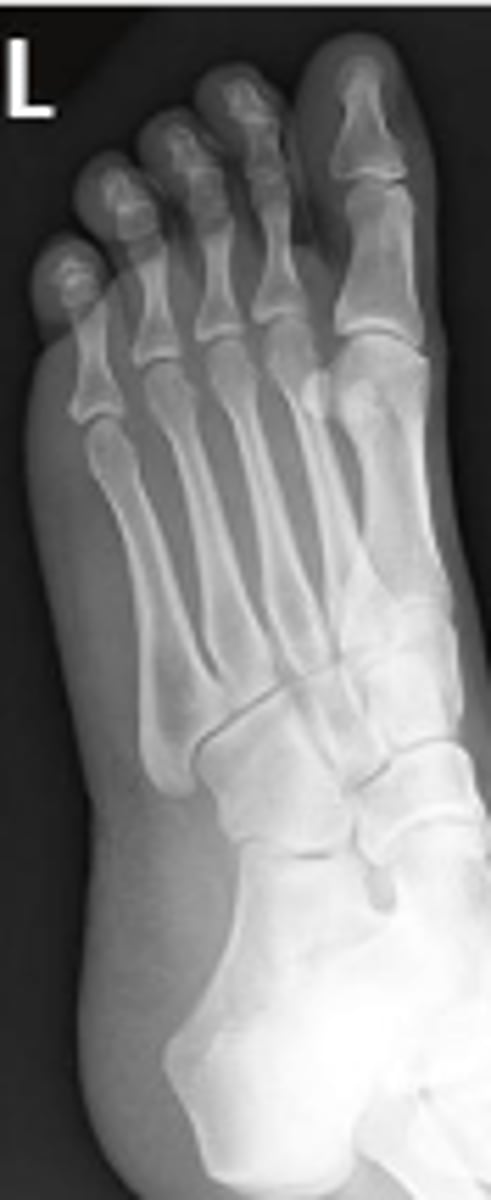

Medial oblique of the left foot

What is the name of the radiographic view?

AP left foot

Navicular of the left foot

What are the arrows pointing to?

5th metatarsophalangeal joint of the left foot